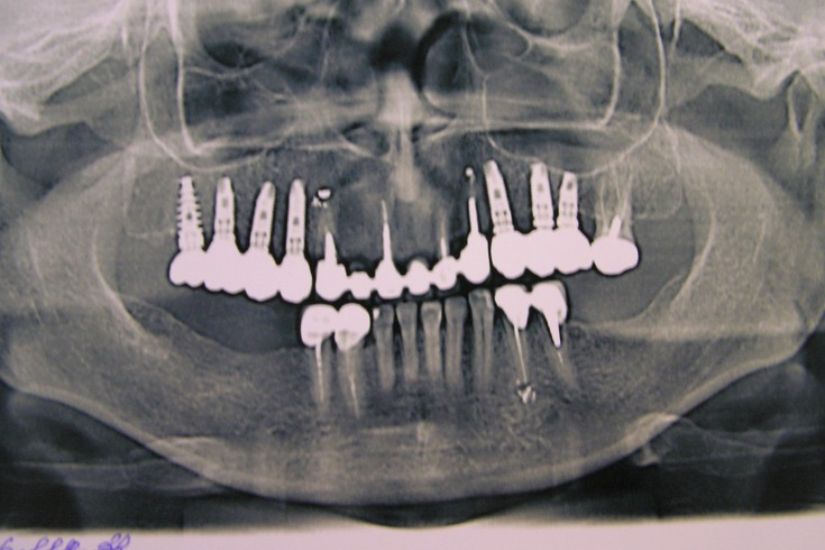

Dental Rehabilitation Using Alpha Dent Implant in Case of Reconstructed Mandible after Excision of Ossifying Fibroma

Dental Rehabilitation Using Alpha Dent Implant in Case of Reconstructed Mandible after Excision of Ossifying Fibroma Dr. Parit Ladani MDS